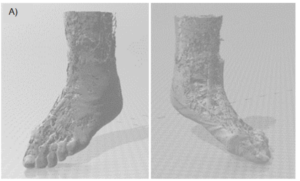

Materialize Mimics Care Suite Research which uses advanced algorithms to process imaging data and reconstruct precise anatomical structures, was then utilized to generate an unrestricted 360-degree viewing model of the foot in a virtual reality environment, allowing for detailed visualization of the shattered ankle bone and its localization, including separation of muscles, soft tissue, and fat. The software also includes features for the integration of virtual reality (VR) and 3D printing, allowing for preoperative rehearsal and the creation of physical prototypes of the anatomy. The QCTDM display provided an effective platform to produce a 3D global view, indicating the optimal locations for the application of fixing screws to avoid loosening post-internal fixation.

A 3D computer model and prototype were designed, produced, and printed by the authors, and were used for preoperative planning. A see-through 3D 360-degree cross-section of the ankle clearly showed the embedded broken pieces in the region of interest, enabling the surgeon to plan a direct approach for the removal of the broken bone with minimal time required for the procedure.